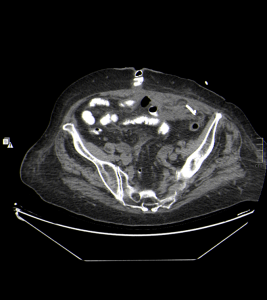

Posteriormente, se realiza un control tras 4 días a partir del momento de la colocación del catéter de drenaje, gracias al cual se obtienen las siguientes imágenes:

Haz click en las imágenes para verlas ampliadas

Se realiza estudio de TC abdominopélvico con contraste oral, se compara con anterior, apreciándose, mejoría, con resolución prácticamente total de la colección de FI izquierda, visualizándose el catéter pig-tail, bien posicionado. No se evidencia dilatación de asas intestinales, se visualiza transito intestinal conservado sin extravasación del contraste.